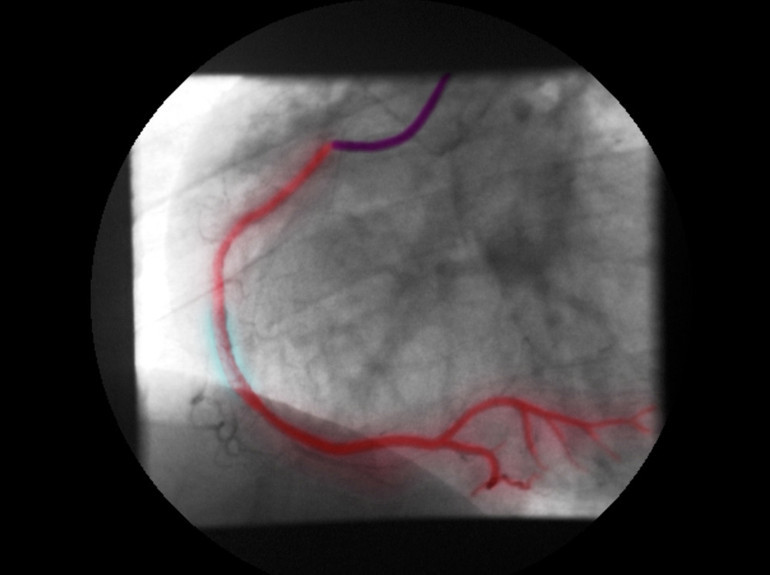

Bilgisayarlı tomografi (BT) / Anjiyografi:

Kullanılan kontrast maddeler iyot (iodine) içerir. Bu maddeler X-ışınlarını güçlü şekilde soğurur.Böylece kontrast verilen bölgeler görüntüde daha parlak görünür.